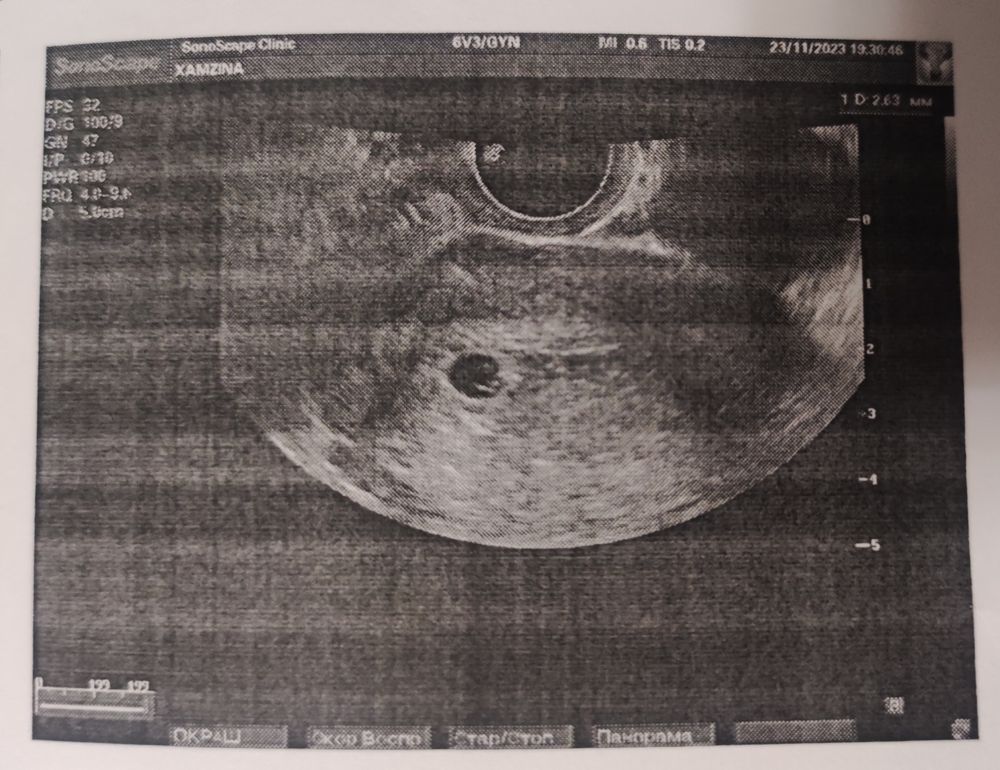

Съездила я на УЗИ, подтвердили беременность 4 недели 🤰🏽Жду недельки две и надеюсь услышать долгожданное сердцебиение. Но это будет адские две недели мучения для меня. Как же очень хочется сообщить родным, но молчу и даже мужу не говорю, боюсь что что то пойдёт не так... Так как в прошлом году под новый так же было УЗИ 4 недели и в итоге беременость замерла😭. Очень верю, что все будет хорошо и никак иначе! В свою очередь чихаю зразным "Арчи" на вас🥰

Фото на память ♥️